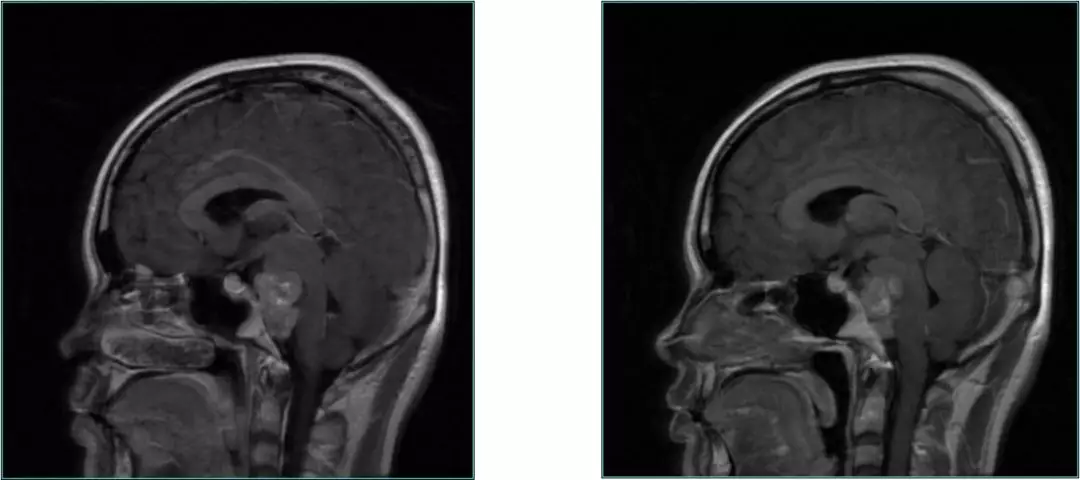

Post-op MRI with contrast

Post-op MRI

General condition is good.

No CSF fistula, double Vision improved.